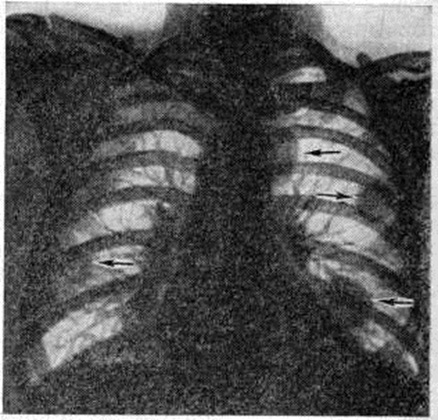

Клинические, признаки поражения внутренних органов отмечаются относительно редко. Помимо перикардита, могут наблюдаться изменения, обусловленные миокардитом (преимущественно очаговым) и эндокардитом. Известны случаи формирования пороков сердца, почти исключительно в виде изолированной недостаточности митрального (левого предсердно-желудочкового) клапана или клапанов аорты; выраженность пороков сердца обычно небольшая, нарушения гемодинамики возникают редко. Поражение лёгких при Ревматоидный артрит включает диффузный фиброзирующий альвеолит, узелковое поражение лёгочной ткани (рисунок 6), васкулит. В ряде случаев отмечается полисерозит (смотри полный свод знаний), который чаще проявляется плевритом (смотри полный свод знаний), перикардитом (смотри полный свод знаний).

Рис. 6. | ||

В дальнейшем присоединяется сужение суставных щелей, эрозии костей, подвывихи и вывихи (рисунок 7, 8). Часто на фоне описанных изменений на краях суставных поверхностей формируются остеофиты — проявление вторичного артроза. Тяжёлое ревматоидное поражение суставов может приводить к их анкилозированию; в случаях особо неблагоприятного течения возможен остеолиз ближайших к суставам отделов костей (рисунок 9). Как редкие рентгенологическое симптомы встречаются периоститы (смотри полный свод знаний), асептические остеонекрозы (смотри полный свод знаний: Остеохондропатия).